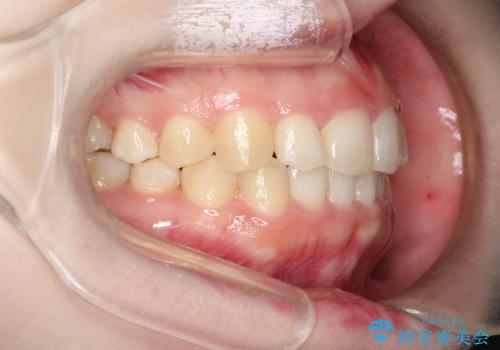

インビザラインでの前歯のガタガタの矯正

- 上下の前歯のがたつきを主訴に来院されました。

歯と歯の間をわずかに削りスペースを作り、インビザラインにて矯正治療を行うこととしました。

使用時間を守っていただけたので、スムーズに矯正を終了することができました。